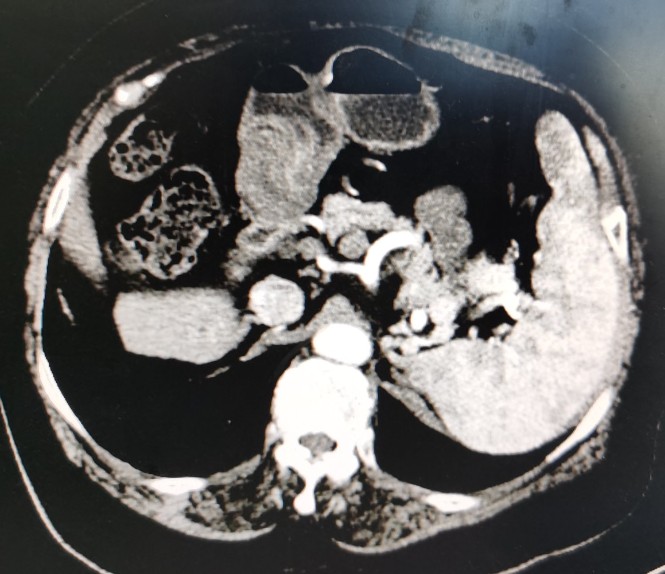

黄婶的肝脏,左右分明,左右肝均萎缩,脾大

萎缩的右肝发展成了肝癌

肝癌向下生长